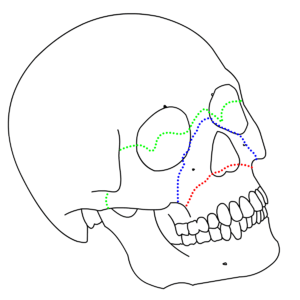

| LeFort I (red), II (blue), and III (green) fractures | |

A Le Fort fracture of the skull is a classic transfacial fracture of the midface, involving the maxillary bone and surrounding structures in either a horizontal, pyramidal or transverse direction. The hallmark of Lefort fractures is traumatic pterygomaxillary separation, which signifies fractures between the pterygoid plates, horseshoe shaped bony protuberances which extend from the inferior margin of the maxilla, and the maxillary sinuses. Continuity of this structure is a keystone for stability of the midface, involvement of which impacts surgical management of trauma victims, as it requires fixation to a horizontal bar of the frontal bone. The pterygoid plates lie posterior to the upper dental row, or alveolar ridge, when viewing the face from an anterior view. The fractures are named after French surgeon René Le Fort (1869–1951), who discovered the fracture patterns by examining crush injuries in cadavers.[1]

There are three types of Le Fort fractures. As the classification increases, the anatomic level of the maxillary fracture ascends from inferior to superior with respect to the maxilla:

- Le Fort I fracture (horizontal), otherwise known as a floating palate, may result from a force of injury directed low on the maxillary alveolar rim, or upper dental row, in a downward direction. The key component of these fractures, in addition to pterygoid plate involvement, is involvement of the lateral bony margin of the nasal opening. They also involve the medial and lateral buttresses, or walls, of the maxillary sinus, traveling through the face just above the alveolar ridge of the upper dental row. At the midline, the inferior nasal septum is involved. Historically, it has also been referred to as a Guérin fracture, although this name is less commonly used in practice.

- Le Fort II fracture (pyramidal) may result from a blow to the lower or mid maxilla. The key component of these fractures beyond the pterygoid plate fractures is involvement of inferior orbital rim. When viewed from the front, the fracture is classically shaped like a pyramid. It extends from the nasal bridge at or below the nasofrontal suture through the superior medial wall of the maxilla, inferolaterally through the lacrimal bones which contain the tear ducts, and inferior orbital floor through or near the infraorbital foramen.

- Le Fort III fracture (transverse), otherwise known as craniofacial dissociation, may follow impact to the nasal bridge or upper maxilla. The salient feature of these fractures, beyond pterygoid plate involvement, is that they invariably involve the zygomatic arch, or cheek bone. These fractures begin at the nasofrontal and frontomaxillary sutures and extend posteriorly along the medial wall of the orbit, through the nasolacrimal groove and ethmoid air cells. The sphenoid is thickened posteriorly, limiting fracture extension into the optic canal. Instead, the fracture continues along the orbital floor and infraorbital fissure, continuing through the lateral orbital wall to the zygomaticofrontal junction and zygomatic arch. Within the nose, the fracture extends through the base of the perpendicular plate of the ethmoid air cells, the vomer, which are both part of the nasal septum. As with the other fractures, it also involves the junction of the pterygoids with the maxillary sinuses. CSF rhinorrhea, or leakage of the nutrient laden fluid that bathes the brain, is more commonly seen with these injuries due to ethmoid air cell disruption, as the air cells are located immediately beneath the skull base.[4]